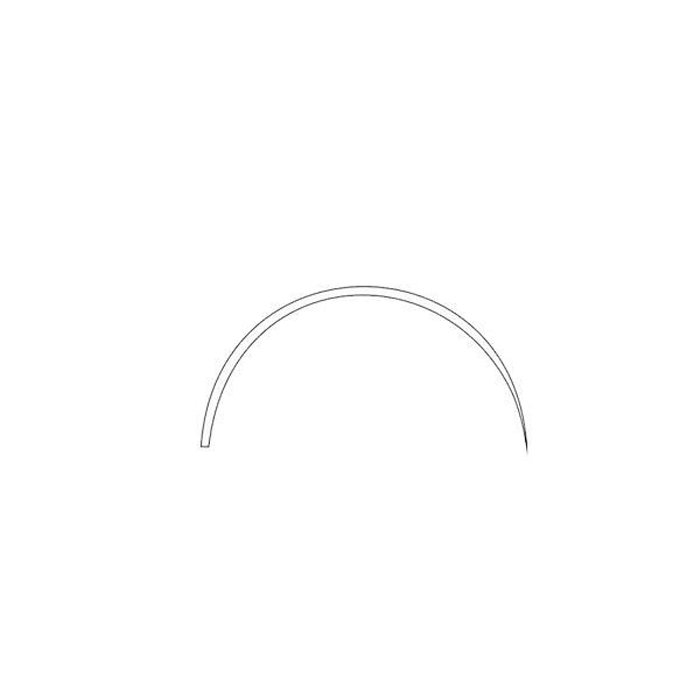

Игла с изгибом 4/8 (полукруглая) и трёхгранной заточкой 4А1 обеспечивает минимальную травматичность тканей и максимальный контроль при проколе. Изготовленная из высококачественной нержавеющей стали, она гарантирует прочность, стерильность и многократное использование после соответствующей обработки.

- Форма изгиба 4/8 (3/8 круга): Оптимальный изгиб для работы в глубоких и труднодоступных ранах. Позволяет выполнять точные и аккуратные проколы с минимальным усилием, обеспечивая хирургу отличный обзор и контроль над движением.

| Тип изгиба | 4/8 (полукруглая, 3/8 круга) |

Цифры обозначают часть круга, которую описывает изгиб иглы. 4/8 — это половина круга (полукруглая), 3/8 — меньший изгиб, 1/2 — аналогично 4/8. Изгиб 4/8 является одним из самых распространенных и универсальных для работы в глубине раны.